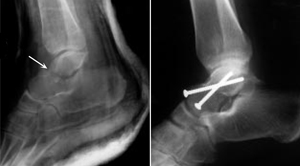

(Left) This x-ray shows a talus fracture. (Right) The bone fragments are fixed in place with screws.

Reproduced with permission from Fortin PT, Balazsy JE: Talus fractures: evaluation and treatment. J Am Acad Orthop Surg 2001; 9:114-127.

If the bones have shifted out of place (displaced), surgery to internally set and stabilize the broken pieces results in the best outcome and reduces the risk of future complications.

Open reduction and internal fixation. During this operation, the bone fragments are first repositioned (reduced) into their normal alignment. They are then held together with special screws or metal plates and screws.